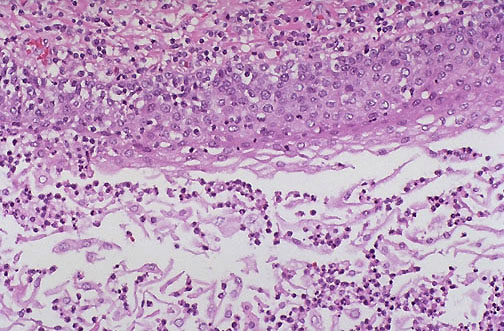

At high magnfication, the mucocele demonstrates acute inflammatory cells in the wall and lumen of the cystic cavity lined by squamoid epithelium.